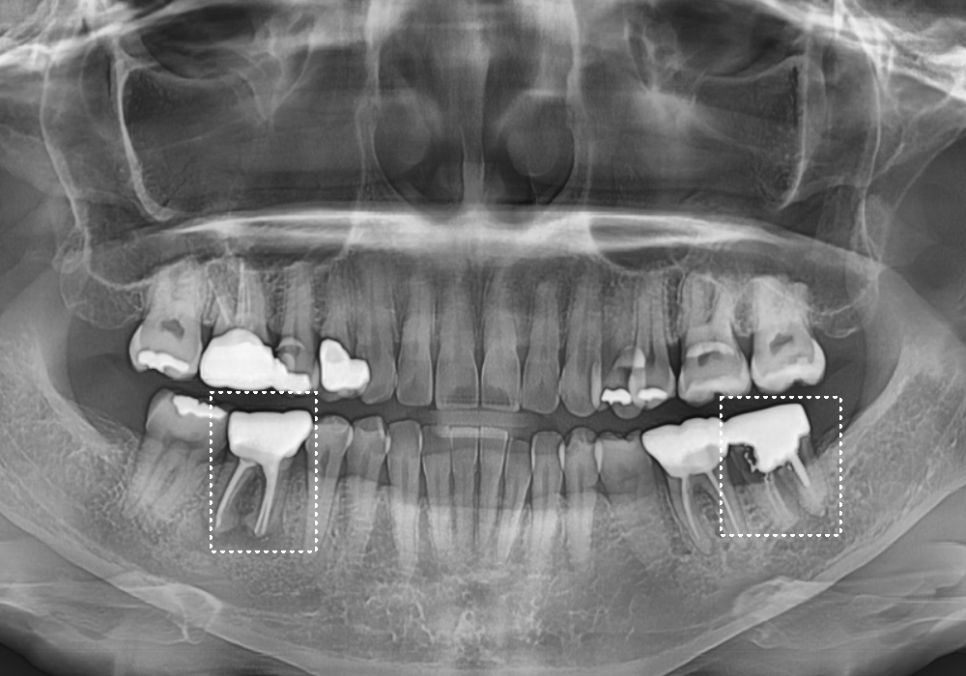

겉으로 보기엔 멀쩡해 보였지만,

방사선 사진을 찍어보니

상태가 생각보다 심각했어요.

예전에 신경치료 후 기둥(포스트)까지 세워

보강했던 치아였는데,

금니 하방으로 2차 충치가

치아 절반 가까이 진행되어

매우 약해진 상태였습니다.

지르코니아로 씌워져 있었지만,

뿌리 끝에 만성 염증이 퍼지면서

주변 잇몸뼈를 야금야금 녹이고 있었죠.

뼈가 녹으니 당연히 치아도